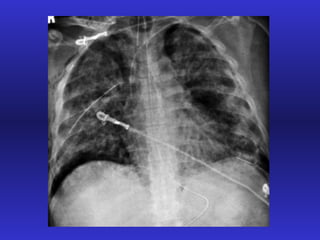

SINDROME DE DISTRESS RESPIRATORIO AGUDO Paradigma de la IR aguda

Definición Injuria pulmonar aguda SDRA  PaO 2 /FiO 2 < 300 < 200 Infiltrados Bilaterales si si PCP < 18 mmHg < 18 mmHg

Distribución del edema en el SDRA